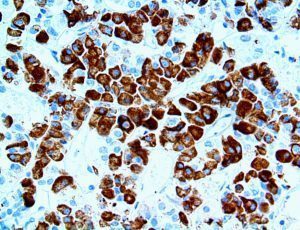

It is the ICU physician who is most likely to witness one of the deadliest manifestations of the abnormal immunological response, the cytokine storm syndrome (CSS). This response is also referred to by some as the cytokine release syndrome (CRS). CSS is characterized by continuous activation and expansion of macrophage and lymphocyte populations, which secrete large amounts of cytokines, causing the cytokine storm. This massive cytokine release is akin to hemophagocytic lymphohistiocytosis (HLH) disease, a syndrome characterized by initial unchecked and persistent activation of cytotoxic T lymphocytes and NK cells.

Clinical and laboratory manifestations of HLH include fever, enlarged liver and/or spleen, neurologic dysfunction, coagulopathy, liver dysfunction, cytopenias (i.e., low levels of erythrocytes, leukocytes, and/or platelets), hypertriglyceridemia, hyperferritinemia, hemophagocytosis, and eventually diminished NK cell activity as the immune system becomes progressively paralyzed. HLH can be familial (primary HLH) or secondary to another disease process (sHLH), such as rheumatic disease, in which it is referred to as macrophage activation syndrome (MAS, characterized by elevated ferritin).